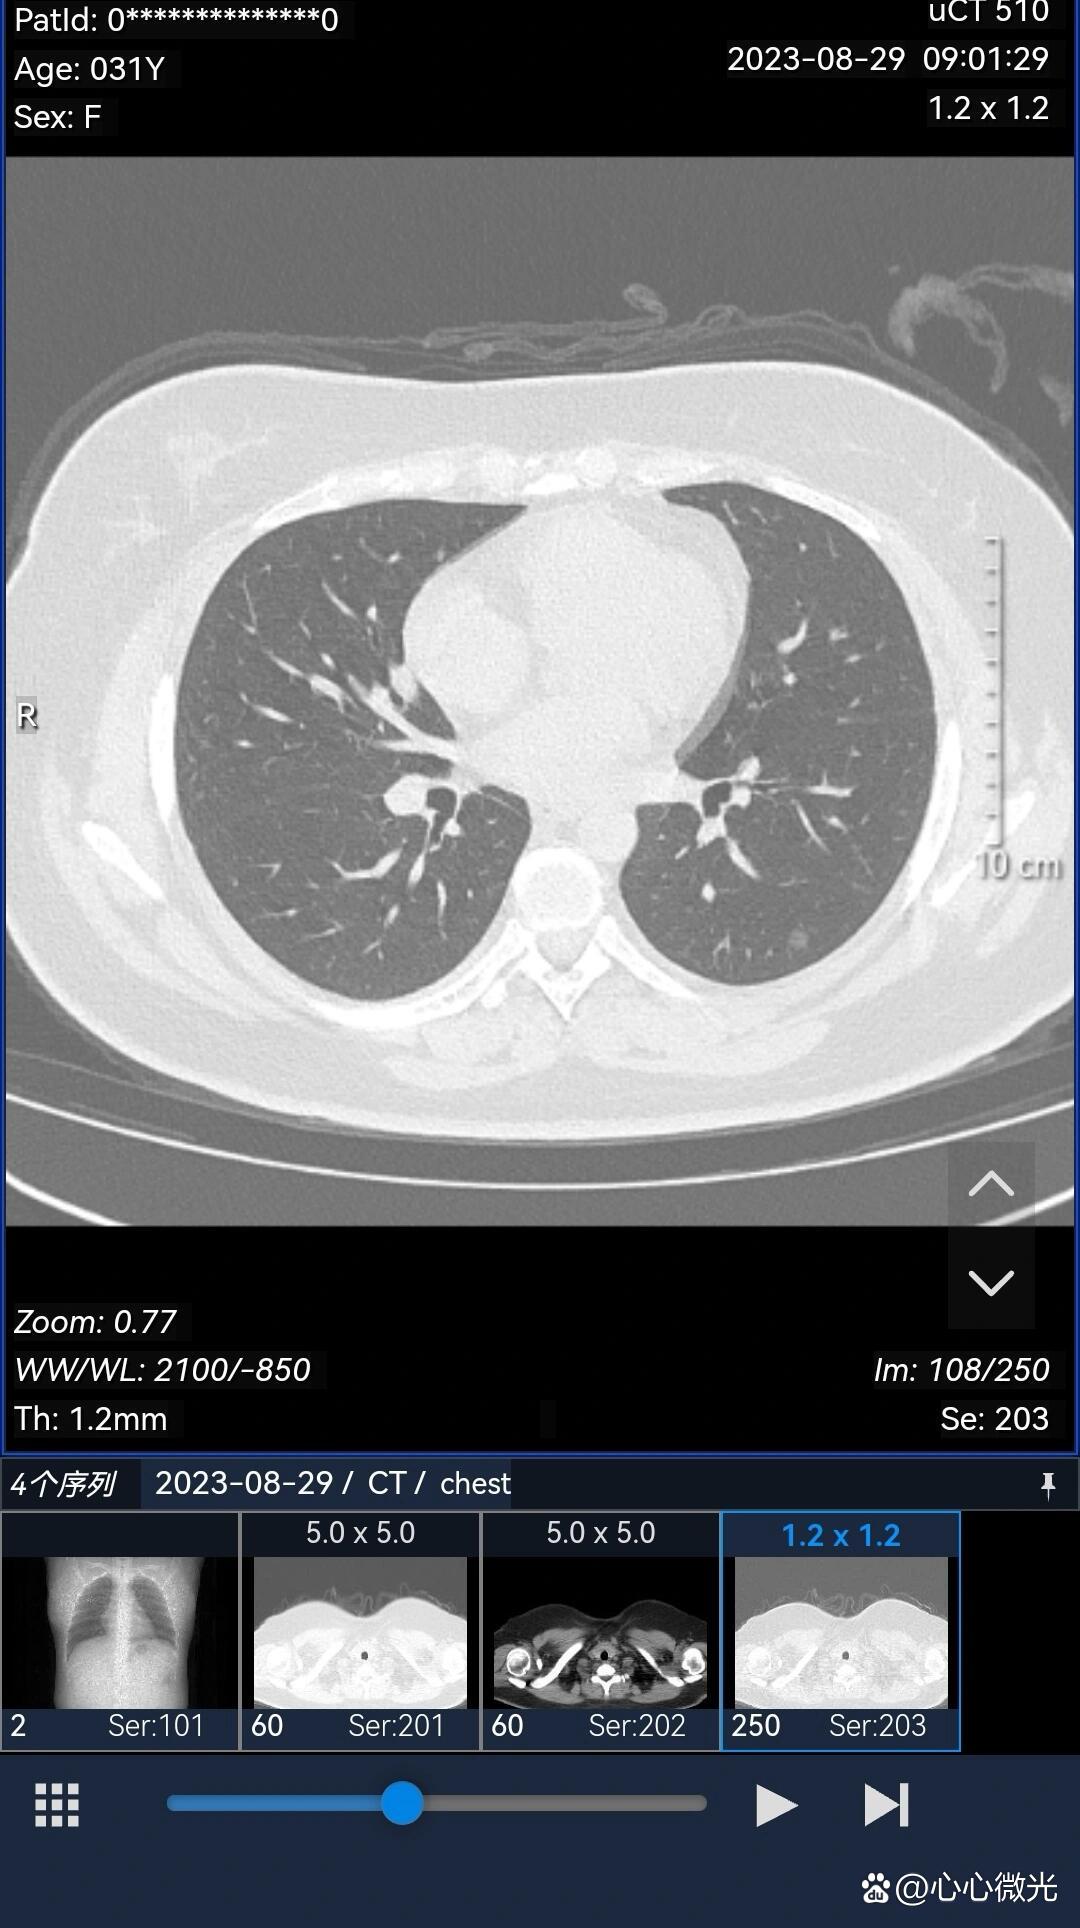

青年女性,实性成分快速增加的混合磨玻璃结节